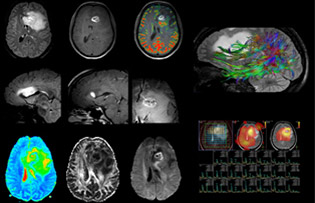

“The biggest challenges are properly characterizing the lesion and giving the surgeon all the information needed, such as the location of vessels and functional areas. Sometimes a very comprehensive exam is necessary, such as when a mass has been discovered at another hospital after which the patient is referred to us. We then do both lesion characterization and preoperative imaging in one exam, so both morphologic and functional assessment. For morphologic assessment we will use pre- and post-contrast T1-weighted imaging, FLAIR to assess infiltration, and diffusion. For functional characterization we will perform perfusion, spectroscopy, and susceptibility weighted imaging to look for micro vessels or micro hemorrhage inside the lesion[4]. For preoperative imaging we perform specific morphologic imaging that is compatible with the navigation system; depending on the location of the tumor, we would do fMRI or DTI.”

“That is the most comprehensive exam we would do. Ingenia has the good spatial resolution and high SNR to provide all this information, and the flexibility to use shorter sequences, so we can do a very comprehensive examination in a limited time.”

32-channel dS head coil a high-resolution solution

The hospital uses the 32-channel dS Head coil for every examination type that doesn’t include the lower neck. “This coil’s biggest advantage is the exceptional SNR. This allows us to use higher acceleration factors than with the standard coil.”

“In some cases, the high resolution that this coil provides is really necessary. For example, in a head and neck case when we look for a small lesion or small vascular conflict, or in IAC imaging or fifth cranial nerve imaging, we want to achieve very good spatial resolution. In brain disease it’s always better to get more details than less. We gain more diagnostic confidence when we have more information.”